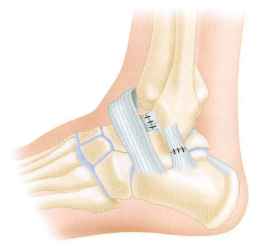

• Anatomia ligamentar da face lateral do tornozelo:

A

• Ligamento talofibular anterior

• Impede a translação anterior do tálus em relação a tíbia

• É avaliado pelo teste da gaveta anterior

• Qual a principal função do ligamento calcâneofibular (face lateral do tornozelo)?

• Restringir o varo do tornozelo

• 2° ligamento mais rompido da face lateral do tornozelo

• Avaliado pelo teste do estresse em varo

• Qual a principal característica do ligamento talofibular posterior ?

• Resistência → dificilmente rompe!